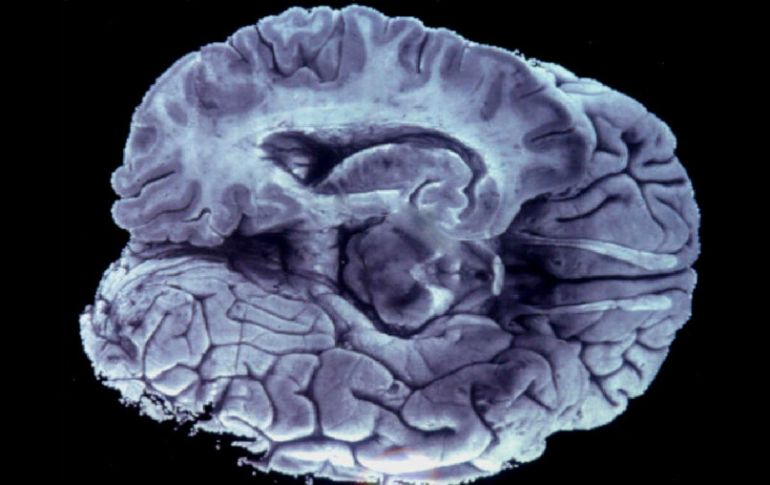

Tecnología | La terapia busca dar una estimulación cerebral profunda Científicos encuentran posible cura para la migraña Pequeños y controlados choques eléctricos podrían ser la solución Por: NTX 8 de enero de 2013 - 08:02 hs El tratamiento reduce el dolor hasta 37 por ciento. ARCHIVO / CIUDAD DE MÉXICO (08/ENE/2013).- Una nueva esperanza para quienes sufren de migraña han abierto científicos de la Universidad de Michigan, en Estados Unidos, al revelar una posible cura a través de pequeños y controlados choques eléctricos. El descubrimiento beneficia a quienes padecen de migraña crónica, toda vez que esta terapia, denominada estimulación cerebral profunda, reduce al dolor de la cabeza hasta 37 por ciento. De acuerdo con una publicación del sitio en Internet en español RT, esta técnica que aplica una corriente eléctrica de dos miliamperios, modifica la velocidad con la que las neuronas reciben un estímulo y dirigen los impulsos nerviosos, y sirve para aliviar el dolor. Los estudios realizados por los científicos recuerdan que los analgésicos que elabora el cerebro humano son los llamados opioides endógenos, mismos que pueden solucionar los dolores más fuertes del cuerpo. Un total de 13 pacientes con migraña crónica, es decir que padecen al menos 15 ataques al mes, les fue aplicada la terapia, que consistió en colocarles electrodos en la corteza motora, y después de diez sesiones el umbral de dolor creció 37 por ciento, acumulado en cuatro semanas. Mediante este descubrimiento los científicos participantes están entusiasmados de que los pacientes dependan menos de los medicamentos contra la migraña y que disminuyan los efectos secundarios. Además, dichos expertos tienen la esperanza de que el procedimiento traiga otros beneficios para desórdenes cerebrales como el dolor crónico, el mal de Parkinson, el temblor esencial o la distonía. Temas Descubrimientos ciencia Sanidad Ciencia médica Lee También Julieta Fierro será homenajeada en la FIL INAPAM: ¿Cómo solicitar un turno para consulta médica gratuita? Nobel de Química premia el desarrollo de estructuras metal-orgánicas Nobel de Física para Clarke, Devoret y Martinis por descubrimiento sobre fenómenos cuánticos Recibe las últimas noticias en tu e-mail Todo lo que necesitas saber para comenzar tu día Registrarse implica aceptar los Términos y Condiciones